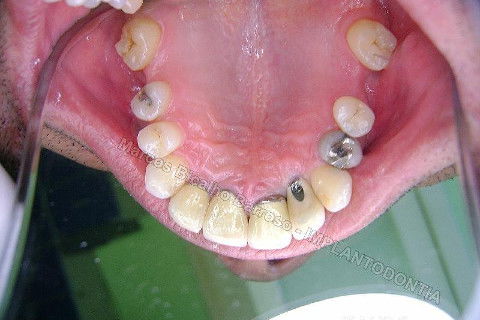

Este caso tem o objetivo de demonstração da técnica que normalmente sigo ; em casos onde ocorre fratura da raiz e consequentemente abscessos, com ou sem formação de fístula. Neste caso fiz a exodontia com preenchimento do alvéolo com biomaterial (osso bovino liofilizado + coágulo do paciente). Após 90 dias, mais ou menos, instalei o implante. Esperei mais 4 meses e realizei ontem (12/11/2010) a instalação do cicatrizador com o cuidado de preservar tecido mole, sem remoção de material, apenas afastando gengiva e "enrolando" a sobra de mucosa em direção a face vestibular, para promover conservação de papila futuramente. Se ocorrer excesso de papila, sem problema, remove-se um pouco, mas a intenção é não deixar faltar, o que resultaria em indicação para enxertos gengivais.

Fotos do caso